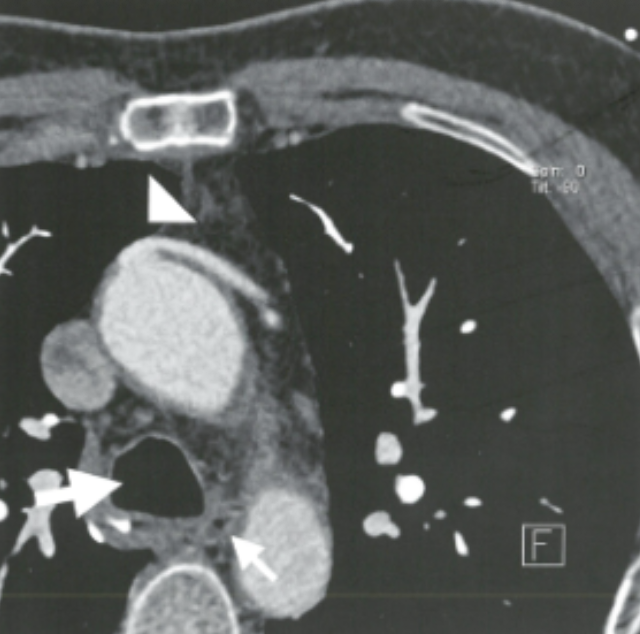

Describe the findings:

Vein Graft (proximal anastomosis)

??Conus branch??